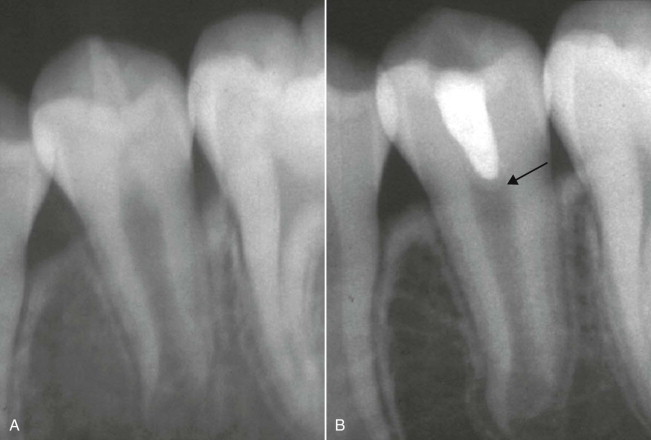

What would present with this kind of radiopaque spot within this tooth?

Dens-in-dente

What is this?

Dens invaginatus